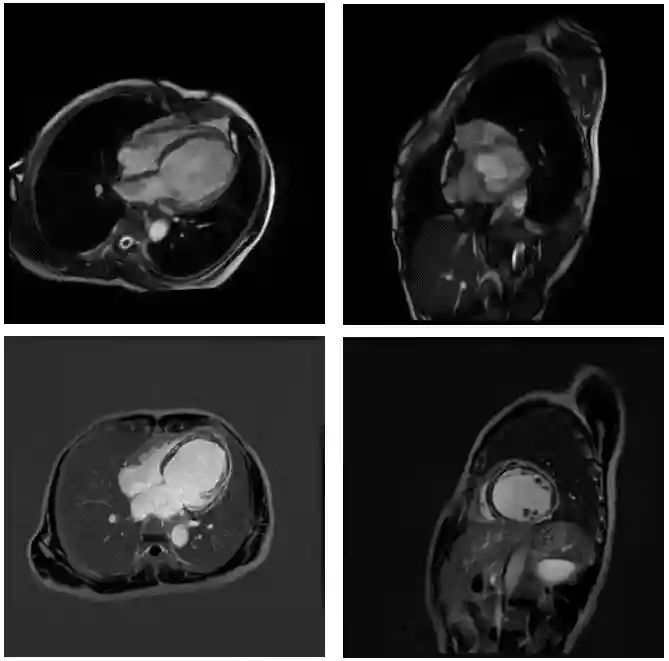

心脏磁共振增强:左心房前后径为35.38mm,右心房前后径为35.74mm,左心室舒张末期内径约为71.27mm,右心室舒张末期内径约为28.35mm。射血分数为(EF)16%,左心室间隔基底段至中段心肌纤维化,考虑非缺血性心肌病。(图1)

图1患者心脏磁共振增强图像